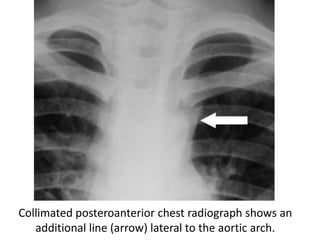

Collimated posteroanterior chest radiograph shows an

additional line (arrow) lateral to the aortic arch.

Collimated posteroanterior chestradiograph shows an additional line (arrow) lateral to the aortic arch.